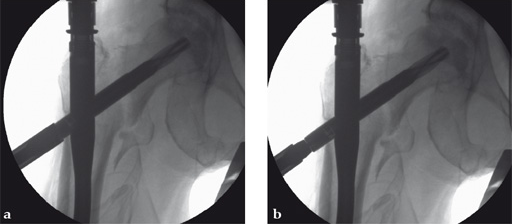

Use of the guide-wire aiming device in an 87-year-old woman.

a Clinical picture of the whole aiming and insertion construct.

b After closed and minimally invasive open reduction with a Hohmann retractor pushing on the anterior aspect of the femoral neck for better axial alignment, the guide-wire aiming device has been mounted to the aiming arm and helps to identify the optimal position of the guide wire in the femoral head.

c The K-wire runs parallel to the chosen line of the aiming device. In AP projection the tip of the blade should be positioned in the center of the femoral head.

d In AP projection the tip of the blade should be positioned in the center of the femoral head, in lateral projection the blade should run parallel to and in middle of the neck and also end dead center of the femoral head. The distance of the tip of the blade to the joint should be approximately 10 mm. No predrilling is recommended in osteoporotic bone.